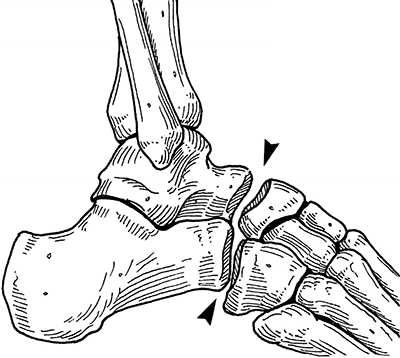

Поперечный сустав предплюсны или сустав Шопара состоит из таранно-ладьевидного и пяточно-кубовидного суставов. В обоих суставах есть фасетки овальной формы, ось которых проходит по наибольшему диаметру овала. В нейтральном положении стопы оси находятся под углом, а в положении пронации стопы оси становятся параллельными. В положении супинации угол между фасетками достигает максимума. Он больше, чем угол в нейтральном положении и чем угол в положении пронации. Головка таранной кости имеет выпуклую поверхность, а головка ладьевидной кости, которая сочленяется с ней, имеет, соответственно, вогнутую поверхность. Площадь фасетки таранной кости больше, чем площадь фасетки ладьевидной кости. В сагиттальной плоскости сустав Шопара расположен на расстоянии 32-36% от крайней точки пяточного бугра.

Рис. 1. Сустав Шопара с наружной и внутренней поверхности

Рис. 2. Сустав Шопара по тыльной поверхности стопы. Сустав включает в себя пяточно-кубовидный и таранно-ладьевидный суставы